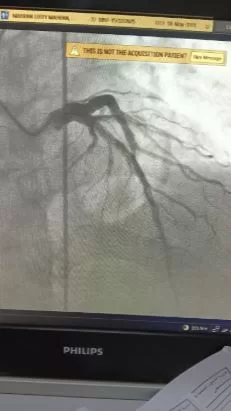

وأُدخلت المريضة غرفة القسطرة القلبية، حيث كشف الفحص التشخيصي عن وجود جلطة بالشريان التاجي تعيق تدفق الدم؛ ليتعامل الفريق الطبي معها ببراعة وينجح في إزالة الجلطة تماماً، مما أدى إلى استقرار الحالة وسريان الدم بصورة طبيعية.